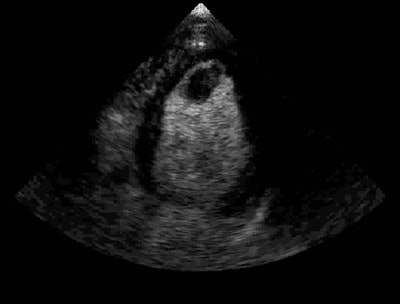

![]() |

| Above: Unenhanced echocardiogram. Below: Echocardiogram enhanced with Definity (Bristol-Myers Squibb Medical Imaging, North Billerica, MA). Image courtesy of Bristol-Myers Squibb Medical Imaging. |